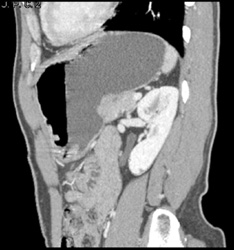

GIST Tumor